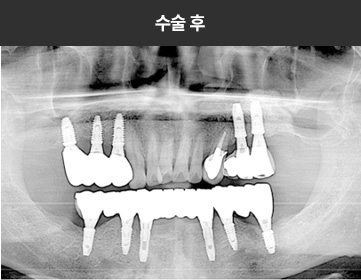

BMP를 이용한 수술 사례      I

치료 기간 : 2023.03.22 ~ 2023.09.15

* 상기 사례의 경우, 해당 의료기관에서 진료를 한 환자분의 동의를 얻어 사용되었습니다. * 치료 전후의 사진은 동일 인물과 동일한 조건에서 촬영 되었음을 알려드립니다.

* 모든 수술 및 시술은 개인에 따라 부작용고지 : 임플란트치료는 치료 후 감염,

염증, 연조직합병증, 출혈, 감각이상 등의 부작용이 있을 수 있습니다.

의료진과 충분히 상의 후 신중하게 결정하시기를 바라겠습니다.